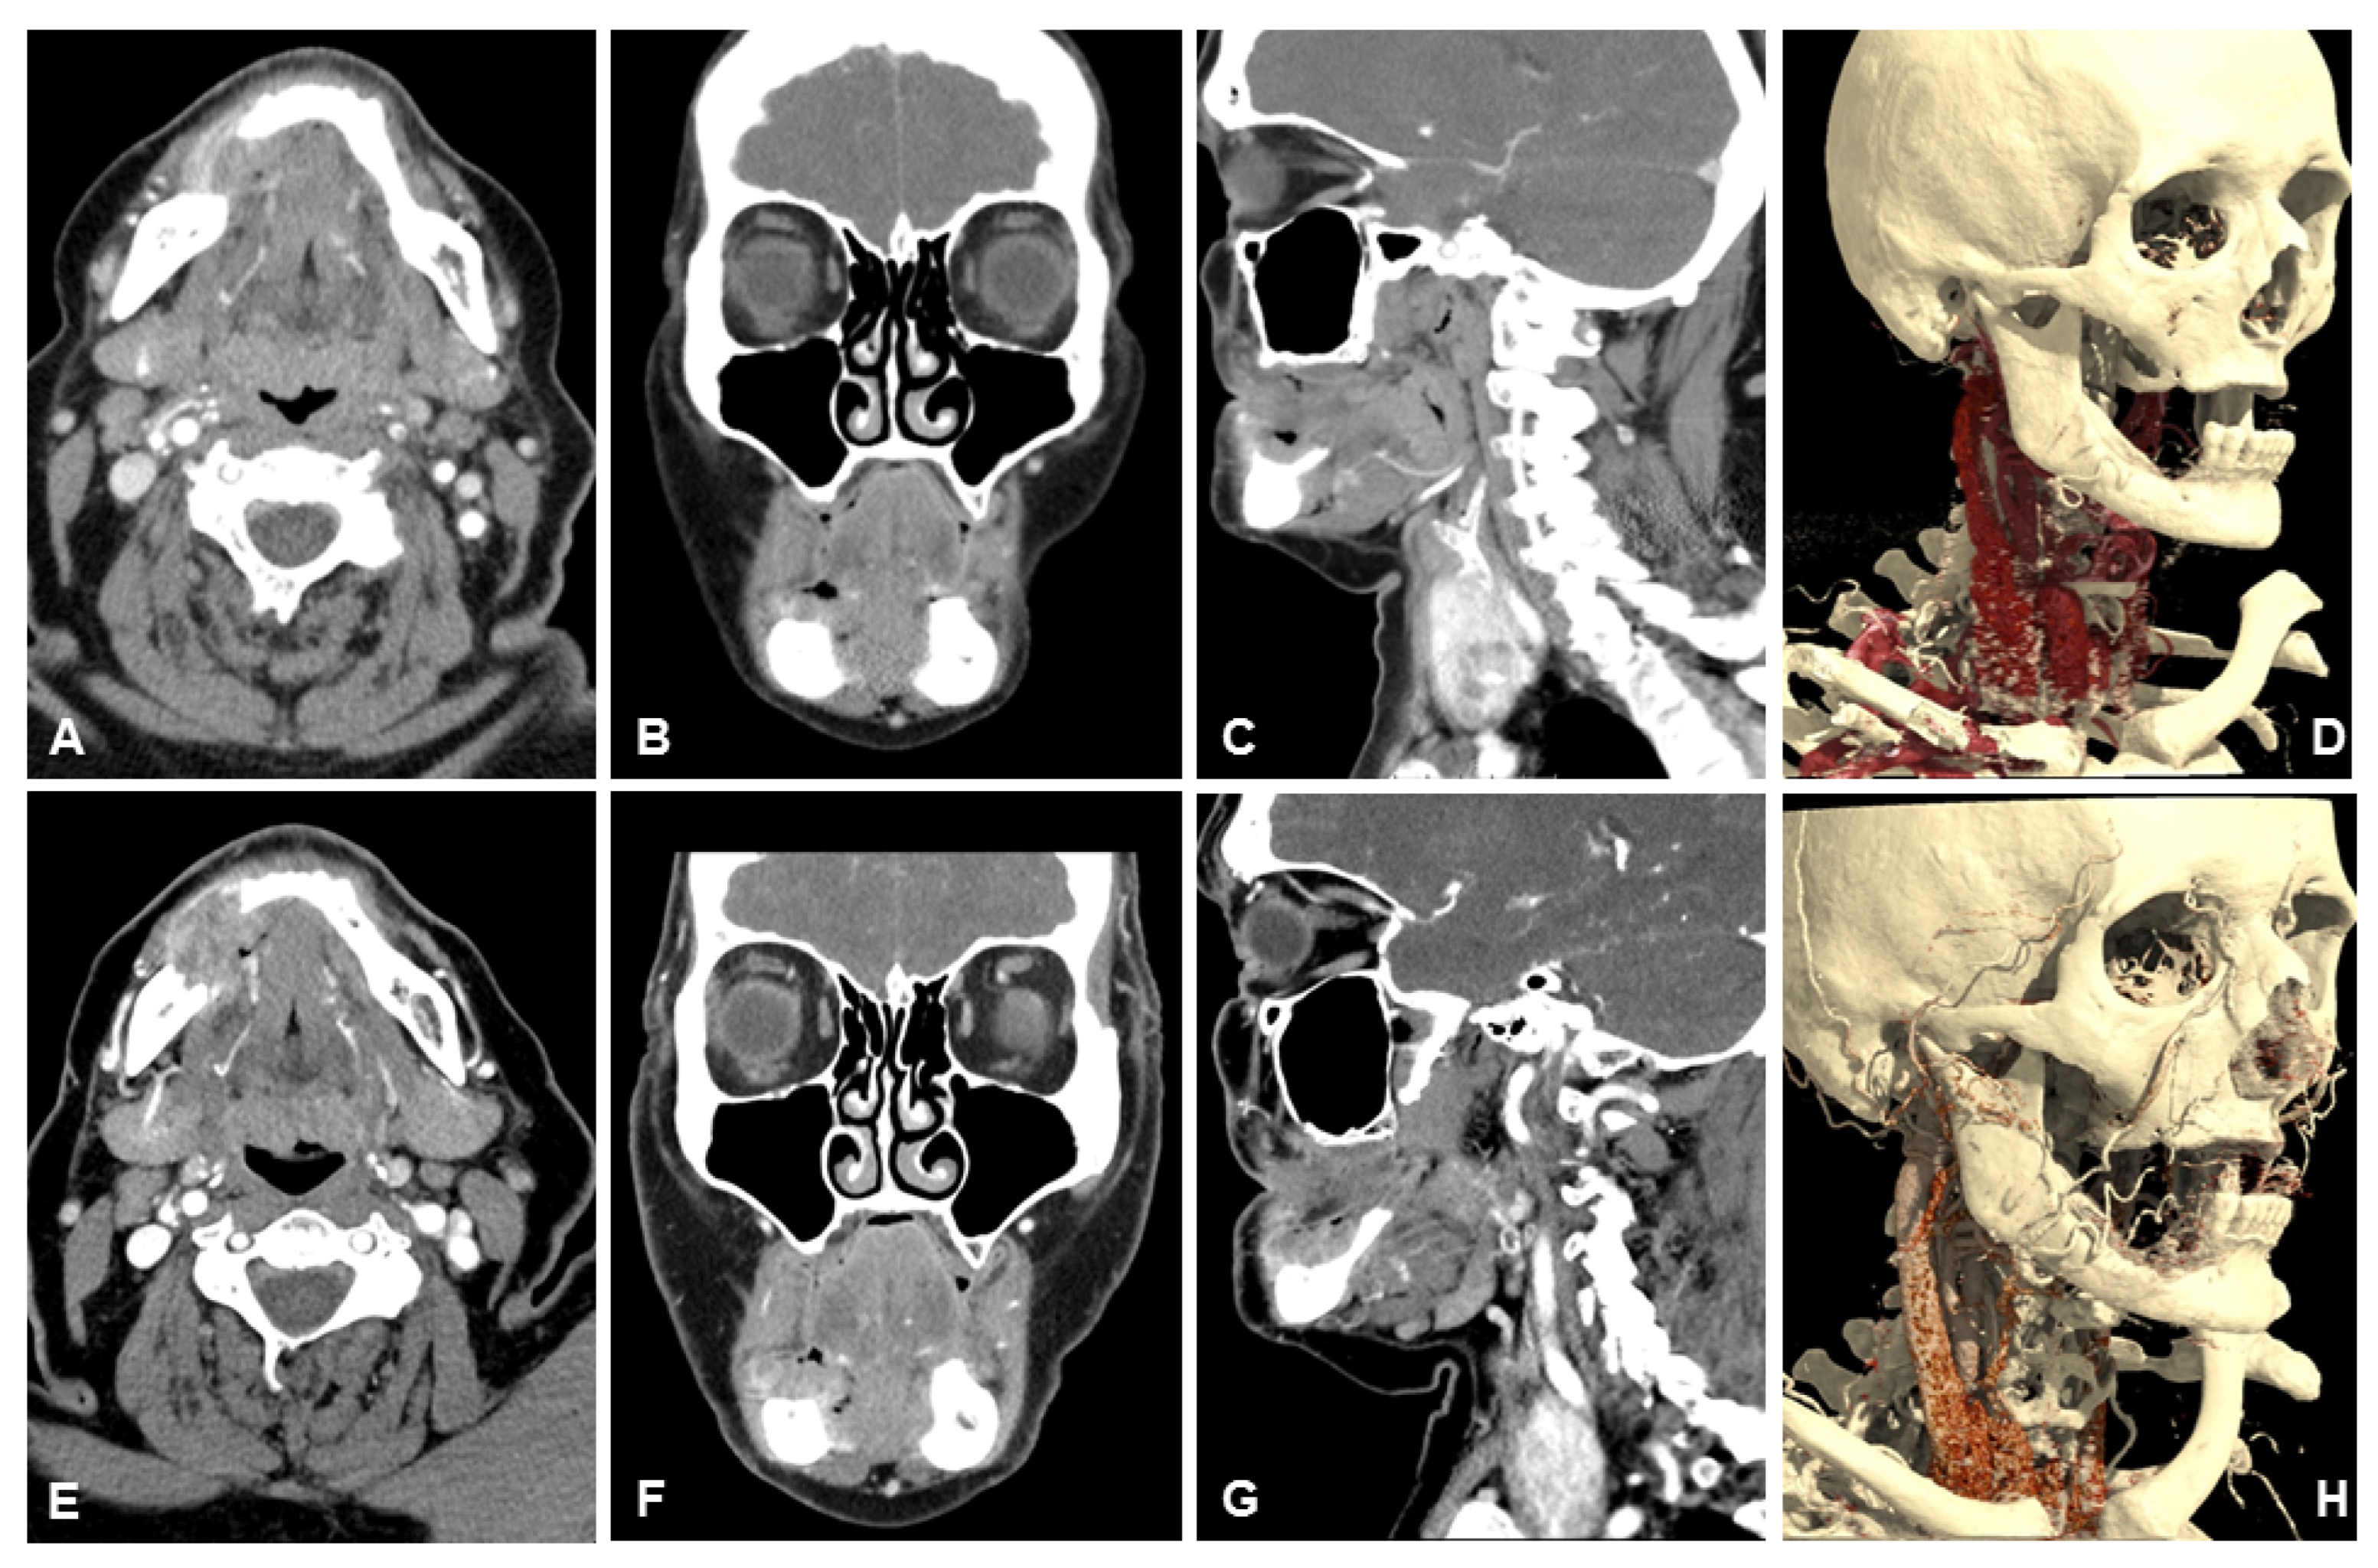

3.2. Subjective Image Quality